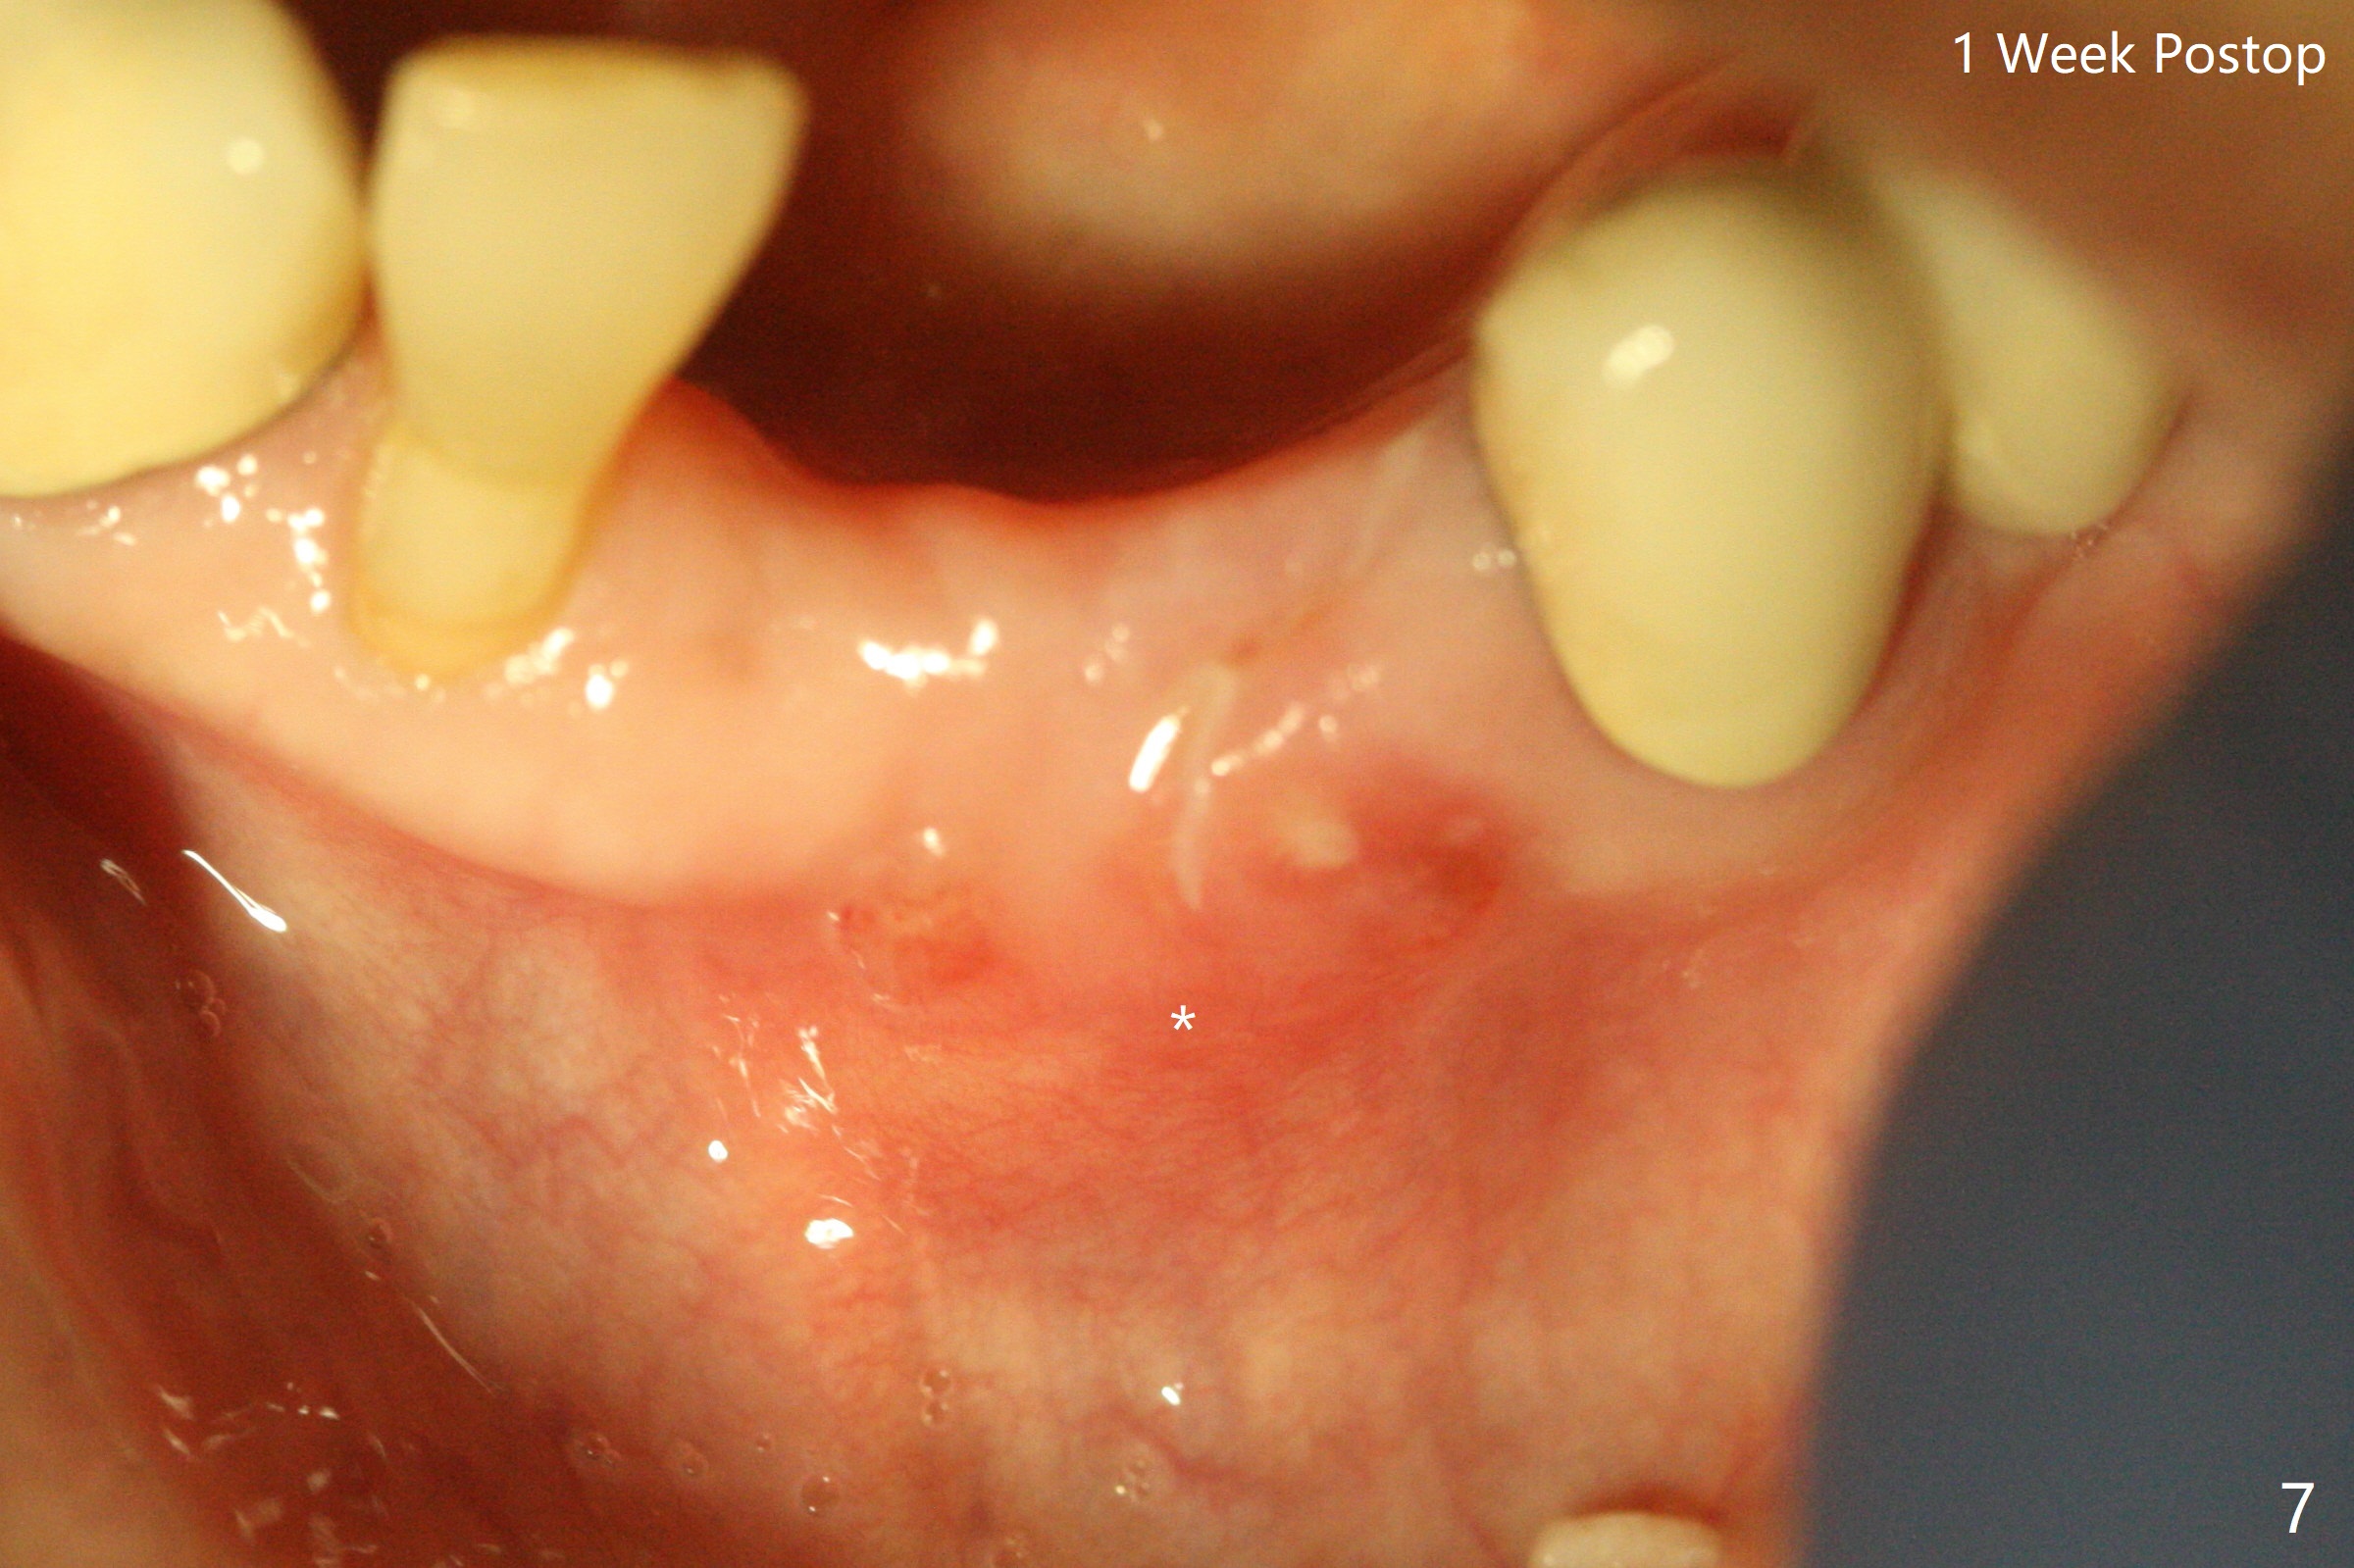

A 64-year-old woman requests extraction of the tooth #23 for lower partial (Fig.1). Since there are 2 buccal sinus tracks, another residual root is suspected (?). After shown loss of the buccal plate (Fig.2,3), the patient agrees to have socket preservation with allograft (Fig.5,6 *) and BioXclude (Fig.4 >). The suspected residual root is not explored considering the 2 sinus tracks being associated with the lesion of #23 (Fig.2,3). Cytoplast is not used because of time constraint and fear of gingival dehiscence associated with extensive dissection. In fact the sinus tracks shrink in a week, while the buccal plate remains bulging (Fig.7 *) and the socket heals (Fig.8 >). The buccal plate is flat (no swelling) 1 month postop (Fig.9).